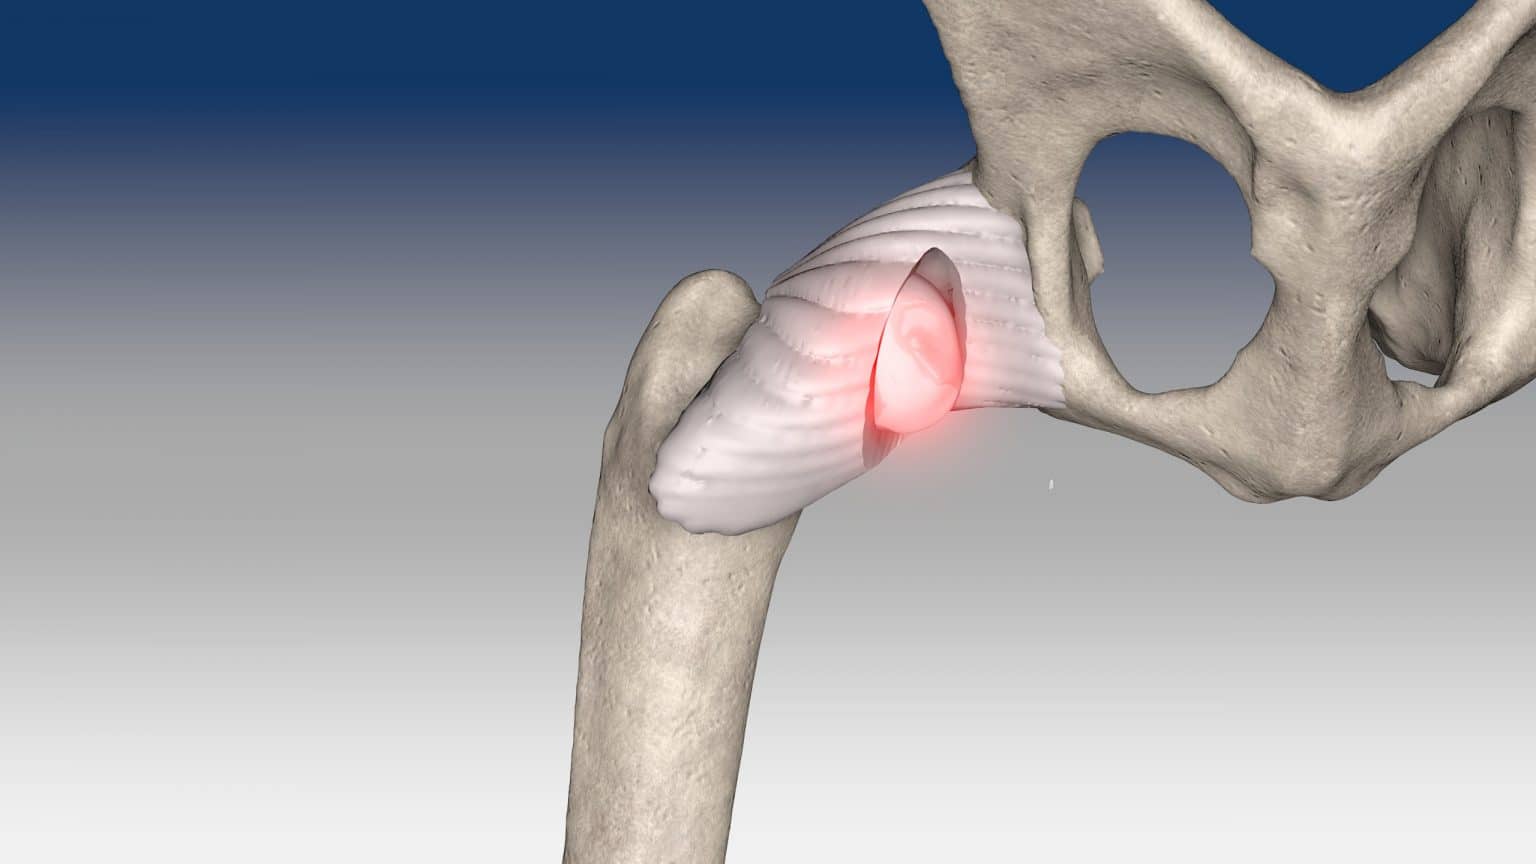

Hip dislocation : Round ligament reconstruction